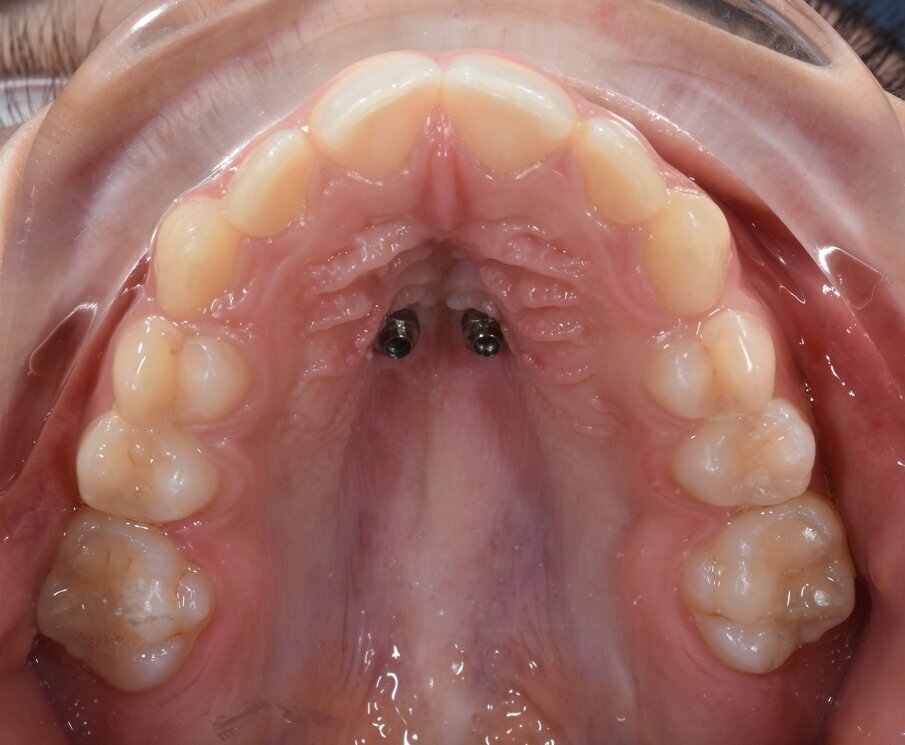

È stata quindi prodotta una dima guida, prodotta con la tecnica additive manufacturing. La dima contiene tutte le informazioni programmate digitalmente per l’inserimento di 2 miniviti BENEfit di 9 mm di lunghezza e 2 mm di diametro. In un’unica seduta sono state posizionate TADs ed espansore palatale ibrido. Il protocollo di attivazioni eseguito ha previsto 5 attivazioni al momento dell’inserimento dell’apparecchiatura, e successivamente 1 attivazione al giorno per 20 giorni. Una volta corretta la trasversalità, il caso è stato finalizzato mediante terapia ortodontica con brackets su entrambe le arcate. Le miniviti e l’espansore rapido palatale sono rimaste in sede per tutta la durata della terapia ortodontica, di circa 20 mesi (Figg. 5a-5d). L’espansione scheletrica mascellare ottenuta è stata di 5,6 mm, evitando compensi dentali sui primi molari (Figg. 6a, 6b).

Fig. 5c_Espansore al termine delle attivazioni e finalizzazione con bracket.

Fig. 5d_Visione occlusale del palato a fine terapia ortodontica.